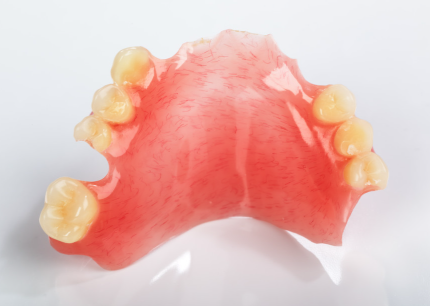

活动义齿

活动义齿列表

活动义齿

活动义齿

活动义齿

活动义齿

活动义齿

活动义齿

活动义齿

活动义齿

活动义齿

活动义齿